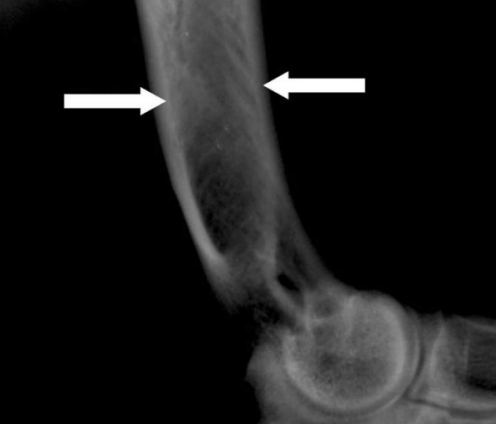

- Early stage

- 영양공 손상되어 어둡게 관찰 (각도에 따라 보이지 않을 수 있음)

- right arrow : 골막하 증식 (신생뼈 → 비교적 뿌얘보임)